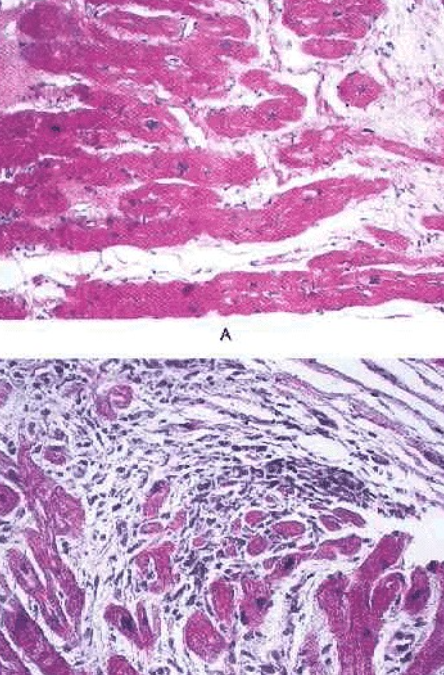

How does Hypertrophic cardiomyopathy present histologically?

Disarrays of hypertrophic degenerated myocytes (unusual angles)

Interweaving arrangement of fibres and interstitial fibrosis

(normal below for reference)